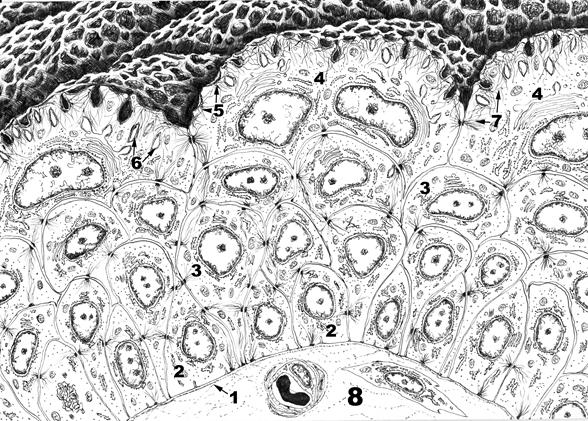

1. Базальная мембрана

2. Базальный слой эпителия

3. Промежуточный слой эпителия

4. Поверхностный слой эпителия

5. Пластинки плазмолеммы

6. Дисковидные пузырьки

7. Микрофиламенты

8. Подлежащая соединительная ткань

Переходный эпителий – особый вид многослойного эпителия, который выстилает большую часть мочевыводящих путей (чашечки, лоханки, мочеточники, мочевой пузырь). Форма клеток и толщина этого эпителия зависят от степени растяжения органа.

Переходный эпителий образован тремя слоями клеток: базальным, промежуточным и поверхностным. Базальный слой образован мелкими клетками, основанием прилежащими к базальной мембране. Промежуточный слой состоит из удлиненных клеток, черепицеобразно накладывающихся друг на друга. Поверхностный слой образован крупными одноядерными полиплоидными или двуядерными клетками (фасеточными клетками), которые в наибольшей степени изменяют свою форму при растяжении эпителия – от округлой к плоской. Этому способствует формирование в апикальной части цитоплазмы этих клеток в состоянии покоя инвагинаций плазмолеммы и дисковидных пузырьков – резервов плазмолеммы, которые встраиваются в нее по мере растяжения клетки. Формированию инвагинаций плазмолеммы способствуют многочисленные микрофиламенты, которые прикрепляются к особым участкам – пластинкам плазмолеммы.

Пластинки плазмолеммы – утолщенные, малопроницаемые для воды участки полигональной формы. Они содержат скопления внутримембранных белковых частиц, каждая из которых образована шестью субъединицами. Пластинки разделены более гибкими участками плазмолеммы, не содержащими белковых частиц, которые способствуют образованию складок. Благодаря такой структуре апикальная плазмолемма поверхностных клеток напоминает булыжную мостовую, за тем исключением, что пластинки представляют собой не выпячивания, а вдавления. Наличие указанных пластинок и плотных соединений между латеральными поверхностями клеток обеспечивает непроницаемость переходного эпителия для воды. Это свойство имеет важное функциональное значение: гипертоническая моча не разводится жидкостью из кровеносных сосудов подлежащей соединительной ткани.